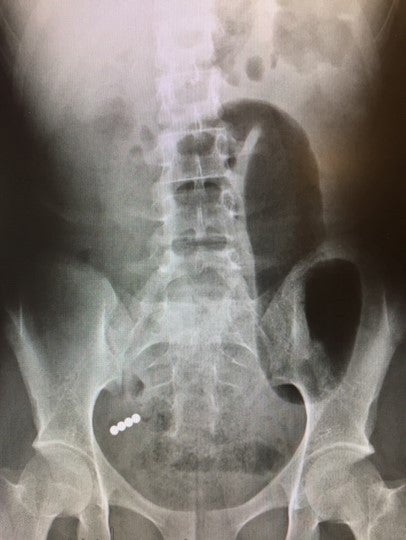

Two common household items – button batteries and rare earth magnets – can cause severe injury and lead to dangerous medical complications if swallowed and not caught quickly.

“Both button batteries and rare earth magnets are small and shiny – a dangerous combination that can tempt a child to put them in their mouth,” says pediatric hospitalist Richard Mazzaccaro, MD, with Lehigh Valley Reilly Children’s Hospital. “While parents might not know the moment their child swallows them, as soon as they notice something is wrong or these items are missing, they should go right to the emergency room.”